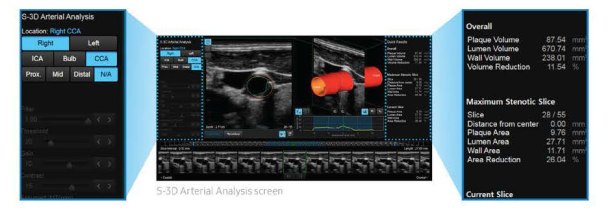

S-3D Arterial Analysis (Innovative volume measurement of arterial plaque)

S-3D Arterial Analysis simplifies volume measurement of arterial plaque, providing 3D vessel modeling.

With Samsung’s S-3D Arterial Analysis, obtaining information on the arterial plaque volume is surprisingly fast and easy even on difficult patients. In addition, it allows medical specialists to track the morphological changes of the artery.